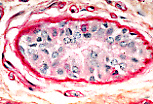

皮肤中分隔表皮和真皮的表皮-真皮连接处的基膜呈PAS阳性。基膜表现为勾勒上皮组织的品红色线条,这种PAS阳性染色是由于基膜区域集中分布的硫酸乙酰肝素(一种蛋白聚糖)所致。 |

所有基膜均呈PAS阳性。例如:血管内皮下方的基膜(本图中为毛细血管),以及包绕外泌汗腺分泌单位的基膜。 |

另一个例子是汗腺管周围的基膜……(可通过双层立方上皮识别)。 |